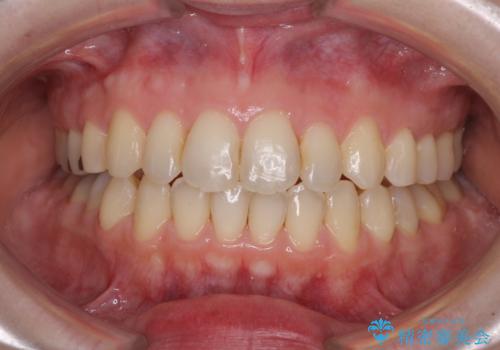

前歯のデコボコを改善 目立たないワイヤー矯正

- 前歯のデコボコを気にして来院された患者様です。

下顎が骨格的にずれており、上下正中を合わせることは難しいことが予想されたため、デコボコの解消を主目的として、ワイヤー矯正を行うこととしました。